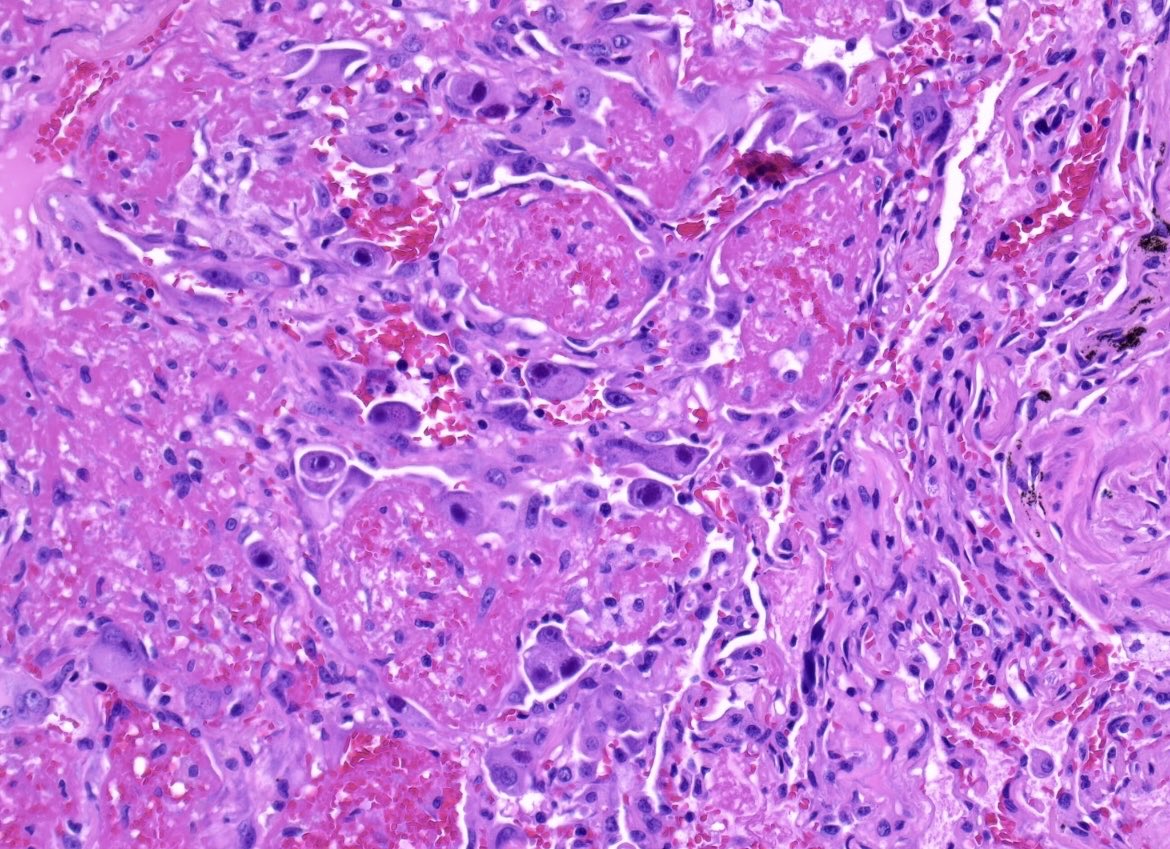

Radical orchidectomy Intratubular embryonal carcinoma with necrosis (in images) There was adjacent mixed germ cell tumour including embryonal carcinoma #PathTwitter #Pathology #PathResidents #GUPath

DrLaurenceGalea's tweet image. Radical orchidectomy

Intratubular embryonal carcinoma with necrosis (in images)

There was adjacent mixed germ cell tumour including embryonal carcinoma

#PathTwitter #Pathology #PathResidents #GUPath